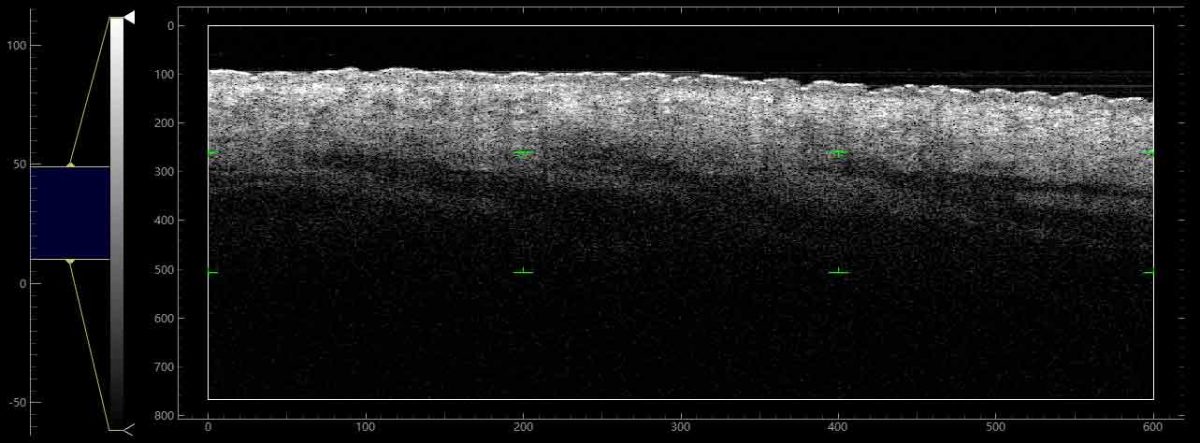

Clairvo Derma is an innovative skin OCT imaging system developed by Clairvo Medical. It enables rapid acquisition of high-resolution cross-sectional skin images, providing clear visualisation of key physiological layers, including the stratum comneum,stratum lucidum, dermal-epidermal junction, and dermal tissue.

Enables clear visualization of the structure and vasculature at depth, allowing clear observation of the physiological structures of the stratum corneum, stratum lucidum, the dermal-epidermal junction, and dermal tissue.